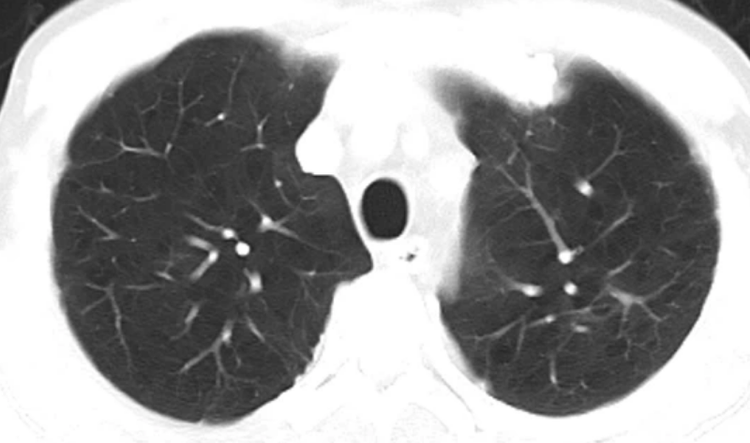

胸部CT

局限性阻塞性肺气肿在CT上表现为局限性肺透明度增加,肺纹理稀少。CT对局限性肺气肿的检出比X线检查更加敏感,可显示阻塞的部位甚至阻塞的原因。弥漫性阻塞性肺气肿表现为两肺纹理普遍稀疏、变细、变直,其余表现同X线胸片所见。